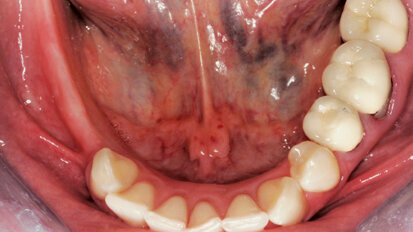

Nový úsměv za jeden den

Čt. 28. května 2020